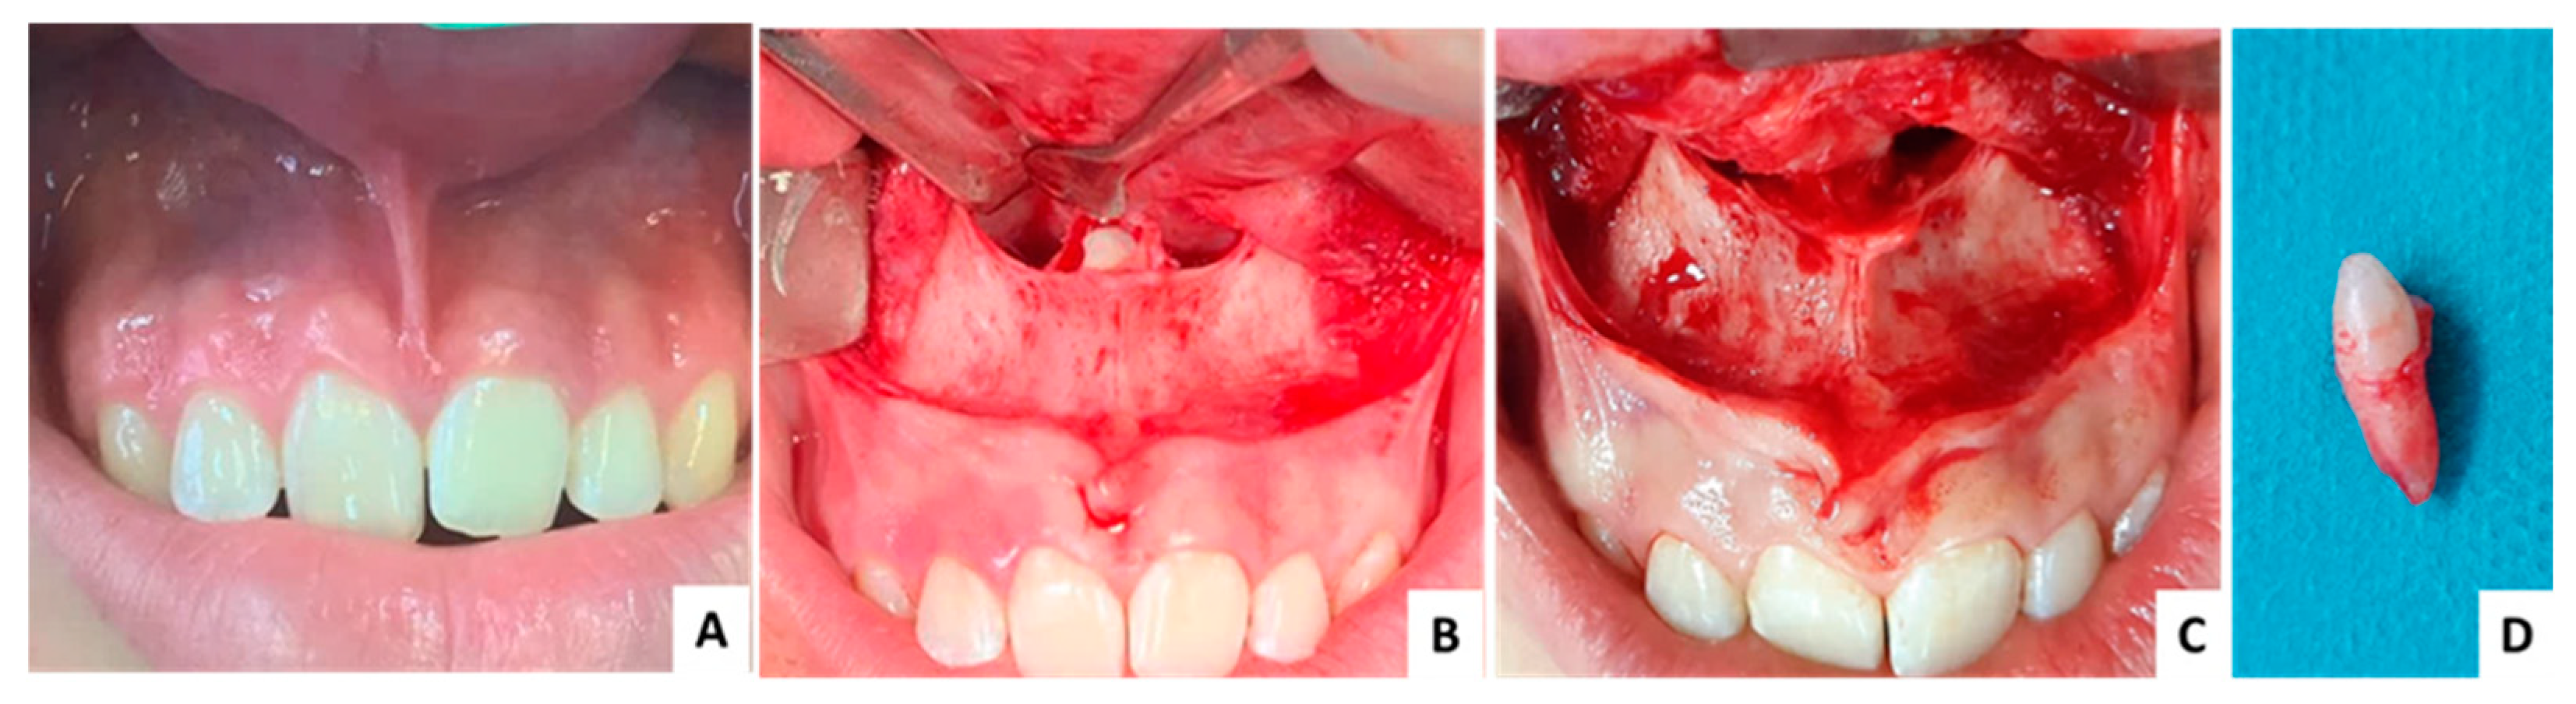

3.1. Case 1 (Figure 3, Figure 4 and Figure 5)

| Case No. | 1 | 2 | 3 |

|---|---|---|---|

| Age (years)/sex | 29/F | 11/M | 16/M |

| Angle formed by the mesiodens axis with the nasal floor | 85.93° | 143.5° | 144.4° |

| Distance from the ANS (mm) | 8.98 | 8.11 | 13.22 |

| Distance to mesiodens from buccal aspect (mm) | 4.71 | 3.70 | 3.84 |

| Distance to mesiodens from palatal aspect (mm) | 6.43 | 5.47 | 6.82 |

| Relation with nasal cavity | Covered with bone | Submucosally | Covered with bone |

| Position regarding nasopalatine canal | In front | In front | In front |

| Operation time (minutes) | 30 | 28 | 31 |

| Complications | No | No | No |